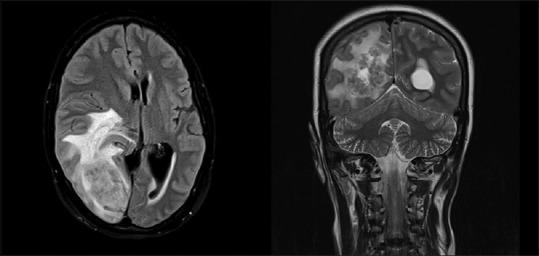

Rare case of meningeal tuberculoma mimicking meningioma in term pregnancy and its management.

https://cdn.ncbi.nlm.nih.gov/pmc/blobs/942c/6130152/1cf99594e828/SNI-9-178-g001.jpg